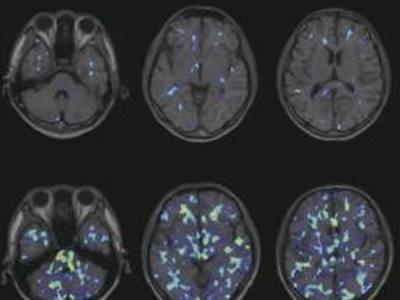

自闭症源于大脑免疫细胞活动过于频繁

自闭症源于大脑免疫细胞活动过于频繁 据日本《东京新闻》11月27日消息,日本浜松...